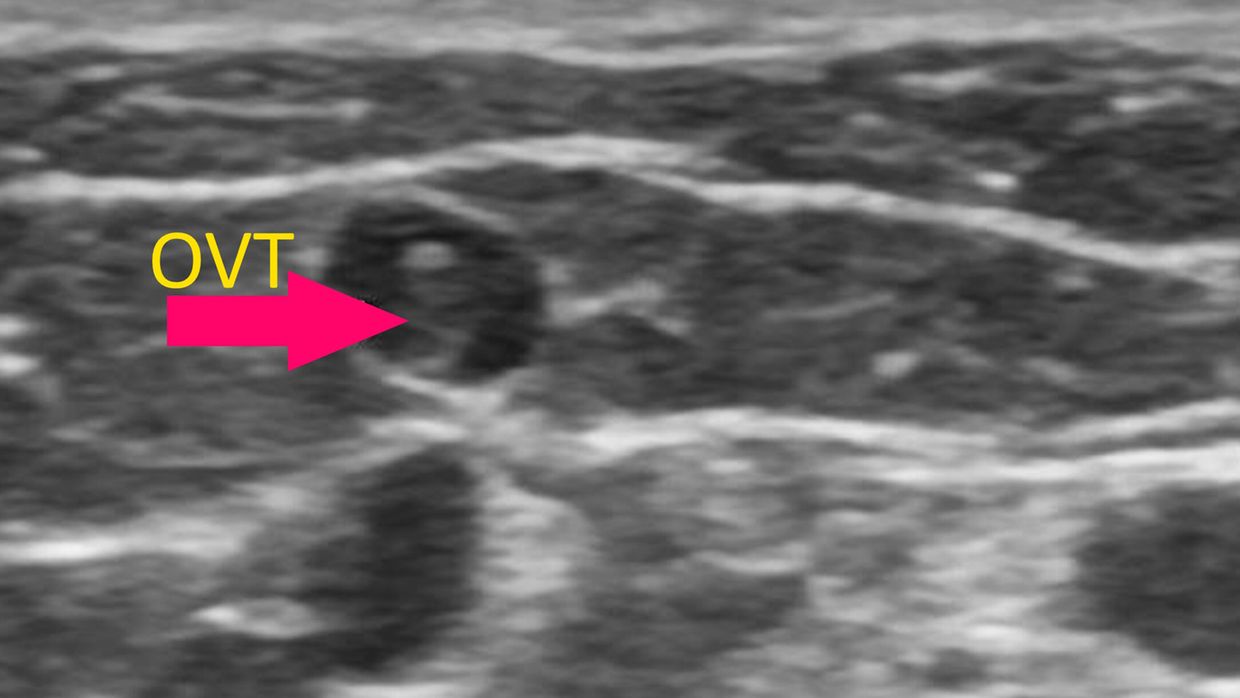

Die oberflächliche Venenthrombose (OVT) und Antikoagulation bei OVT

Allgemeinmedizin | Dermatologie | Innere Medizin | Kardiologie & Gefäßmedizin

| gültig bis April 2027

| 2

DFP Punkte